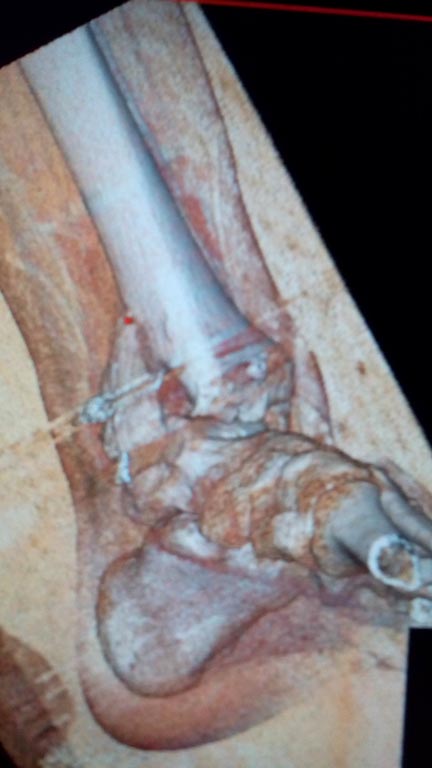

Мужчина, 1987 г.р. получил травму 10.2014. ДТП. Закрытый двухлодыжечный перелом костей костей левой голени, перелом заднего края большеберцовой кости с подвывихом стопы кзади, кнаружи.

Наложен дистрактор. Операция 10.2014: закрытая репозиция, остеосинтез спицами, винтами. В дальнейшем произошло ожидаемое усугубление нарушений взаимоотношений в голеностопном суставе.

Какой план лечения,на Ваш взгляд, предпочтительнее в данном случае? Возможно ли одномоментно устранить подвывих или только на аппарате Иллизарова? Первичные снимки после травмы отсутствуют. Критично ли "растоптана" латеральная суставная поверхность большеберцовой кости?

Мне кажется, что вопрос, поставленный Вами: "Возможно ли одномоментно устранить подвывих или только на аппарате Иллизарова?", отражает не совсем ясное понимание ситуации. Что значит устранить подвывих? А пластику ложных суставов внутренней лодыжки и заднего края большеберцовой кости не нужно делать? И ось голеностопного сустава нужно исправлять. То есть делать остеотомию наружной лодыжки (если она срослась, по снимку не очень понял). Артродез голеностопного сустава в такой ситуации очень сложен. Если же добиться сращения всех переломов в правильном положении, артродез вполне можно отсрочить на несколько лет, что для молодого пациента достаточно важно. Но в конечном счете все определяется Вашим умением и ясным представлением того, чего Вы хотите добиться своей операцией. Во вложении - в чем-то похожий случай. Оперировал эту пациентку 23 лет 11 лет назад через 8 месяцев после похожего на представленный Вами остеосинтез. На первой операции перелом малоберцовой кости в нижней трети был просто не замечен. За счет восстановления оси быстро развившийся артроз протекал благоприятно. В результате артродез был выполнен только в прошлом году, через 10 лет после второй операции. И боли беспокоили пациентку только в течение года перед артродезом.